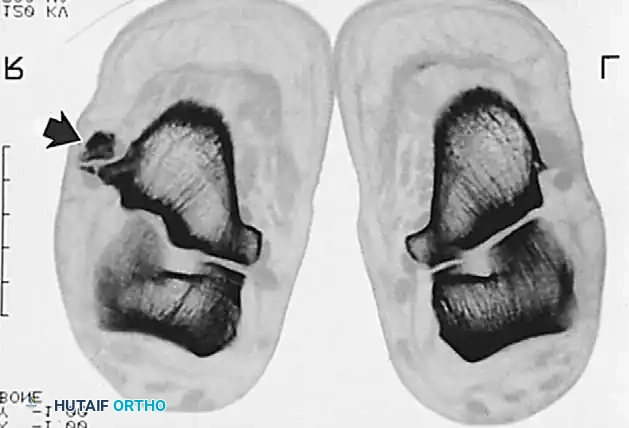

Imaging Modalities

Radiographic examination is indicated to assess for instability, osseous avulsions, and structural alignment. Plain films must be inspected carefully for bone densities in adjacent soft tissues, such as a "fleck sign" indicating SPR avulsion, or proximal migration of the os peroneum indicating a peroneus longus rupture.

While bone scans and computed tomography (CT) can be helpful for osseous pathology, Magnetic Resonance Imaging (MRI) and dynamic ultrasound are the gold standards for soft tissue evaluation. Grant et al. demonstrated the high sensitivity and specificity of ultrasound for evaluating peroneal tendon tears, allowing for dynamic assessment of subluxation. MRI provides excellent visualization of tenosynovitis, tendon morphology, and longitudinal split tears.

Krause and Brodsky Classification

Surgical decision-making for peroneus brevis tears is heavily guided by the intraoperative assessment of tendon viability. Krause and Brodsky classified tears of the peroneus brevis into two distinct types:

* Grade I: Involves 50% or less of the cross-sectional area of the peroneus brevis tendon.

* Grade II: Involves more than 50% of the cross-sectional area of the tendon.

This classification directly dictates whether the tendon can be salvaged via tubularization (Grade I) or requires excision and tenodesis (Grade II).